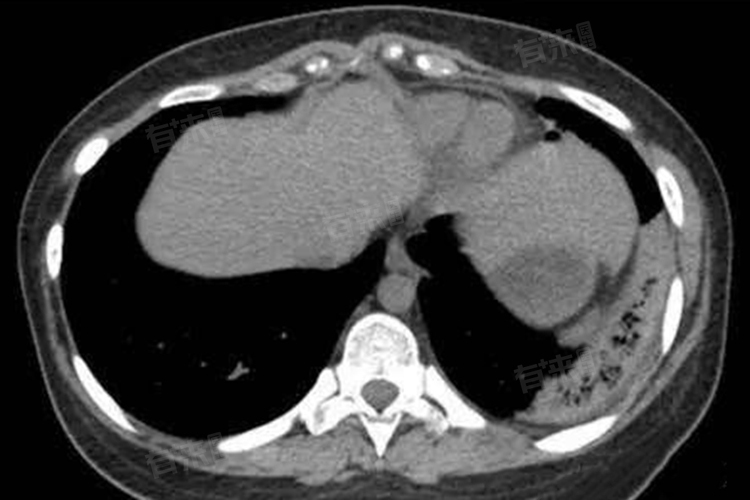

肺出血性梗死是指肺部出血,并且有血栓形成,导致肺部血液循环受阻出现淤血。由于梗死灶内有大量出血,所以被称为出血性梗死。肺出血性梗死是一种严重的肺部疾病,需要及早诊断和治疗。